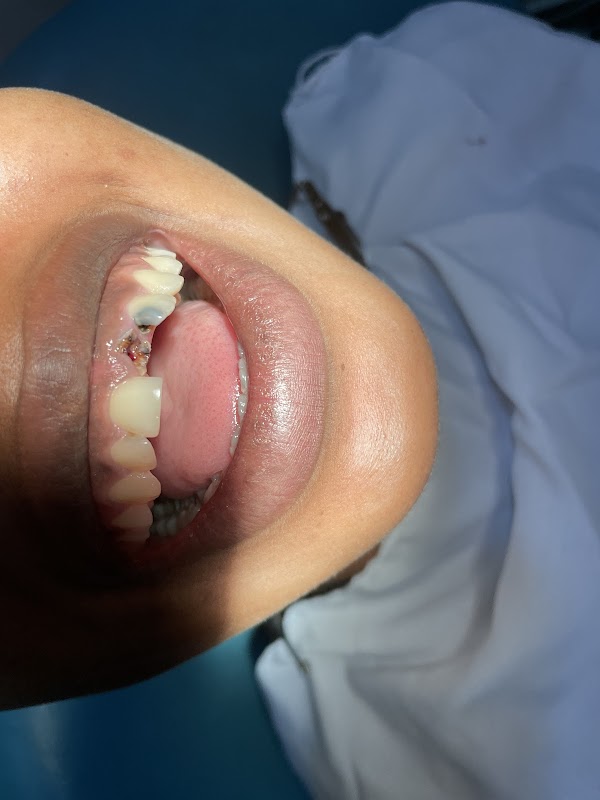

Présentation

Photos